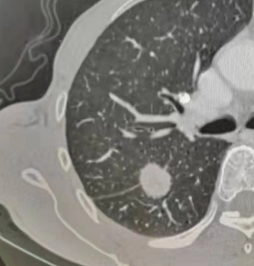

纯磨玻璃结节(类似荔枝果肉)、混合磨玻璃结节(类似荔枝果肉与果核并存)(恶性风险较高)、实性结节(类似荔枝果核)。

纯磨玻璃结节 | 混合磨玻璃结节 | 实性结节 |